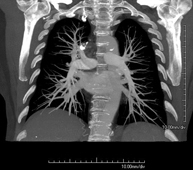

- Pulmonary Artery CT angiography (PTE Study, Pulmonary Thromboembolism)

Diagnostic test to examine the pulmonary arteries using CT (Computed Tomography) equipment to obtain two- and three-dimensional images. The use of iodinated contrast is essential in this study, as it will allow for better anatomical definition. This test is mainly indicated in cases of suspected pulmonary thromboembolism (PTE) to rule out or confirm the presence of blood clots inside the arteries.

Prova diagnòstica que consisteix en l'estudi de les artèries pulmonars mitjançant l'ús d'un equip de TC (Tomografia Computeritzada) per obtenir imatges bi i tridimensionals. En aquest estudi és imprescindible l'ús de contrast iodat que permet una millor definició anatòmica. Aquesta prova està principalment indicada en els casos de sospita de tromboembòlia pulmonar (TEP) per descartar o confirmar la presència de coàguls sanguinis a l'interior de les artèries. - TC Tòrax d'alta resolució